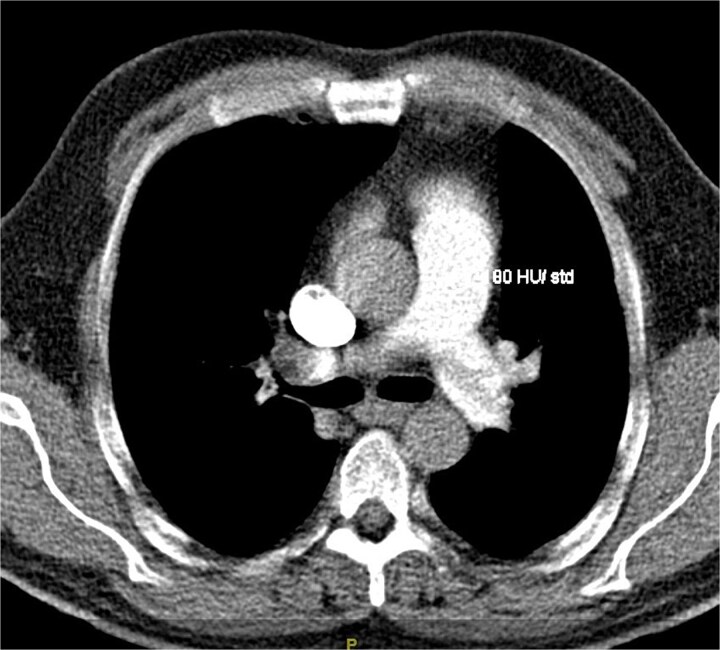

默克尔细胞癌(MCC)是一种罕见的侵袭性神经内分泌恶性肿瘤,通常出现在皮肤,并迅速进展到其他身体部位。MCC通常出现在阳光照射的区域,主要是头颈部以及上肢和肩部。它通常影响皮肤白皙的老年男性。在这个报告中,我们提出一个不寻常的MCC病例,一个48岁的白人男性,最初的表现是一个巨大的肺栓塞。患者的进一步检查显示没有典型的MCC皮肤表现,而是疾病转移。本报告的目的是强调即使患者没有常见的MCC危险因素或皮肤表现,也应将MCC视为鉴别的重要性。

Merkel cell carcinoma (MCC) is a rare aggressive neuroendocrine malignancy that typically presents in the skin and rapidly progresses to other body parts. MCC is typically found in sun-exposed areas, mainly the head and neck region as well as the upper limbs and shoulders. It typically affects fair-skinned elderly males. In this report, we present an unusual MCC case of a 48-year-old Caucasian male with an initial presentation of a massive pulmonary embolism. Further work-up of our patient indicated no typical MCC skin presentation, but rather metastases of the disease. The goal of this report is to highlight the importance of considering MCC as a differential even when patients do not present with common MCC risk factors or skin presentations.